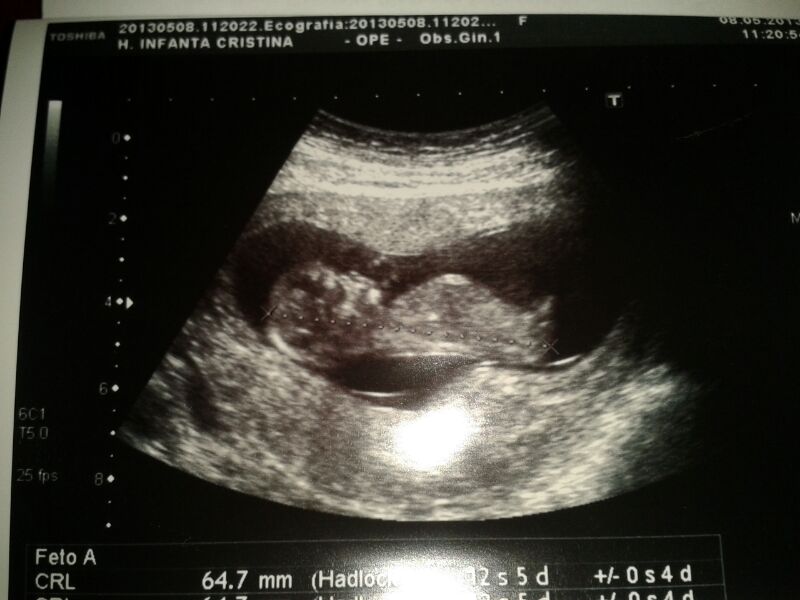

De las cosas más lindas que he experimentado, «la primera ecografía». Yo este momento lo llamo el antes y el después, hasta la semana 11 nadie realmente me había confirmado que un

ser estaba creciendo dentro de mi, lo sabia, pero no existía prueba científica de que esto fuese así, y yo necesito de pruebas, ver para creer, esa soy yo! Así que cuando llego al médico la primera vez, me acuesto en la camilla y empieza a aparecer esa criatura en una pantalla a mi derecha, luego de repente escucho los latidos de su corazón, y ahí es cuando piensas, «mierda, ahí esta, voy a ser mamá». A partir de ahí sólo vi lo maravilloso de ese pedacito de ti que esta formándose dentro y que es capaz de producir tantos sentimientos encontrados, el más fuerte claro esta es el de felicidad.